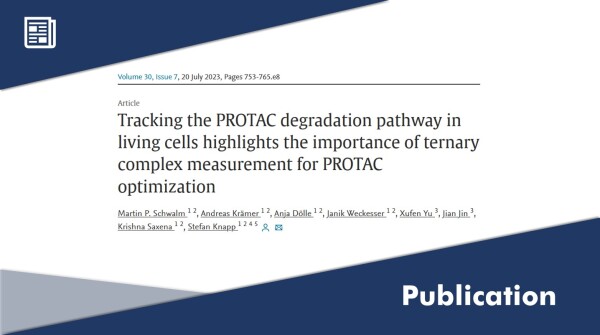

20.07.2023 - 12:36:24

Cell-Based Assays for PROTAC

There is a new paper published in Cell Chemical Biology, featuring the cover. Martin Schwalm from the Knapp lab (B03) and

...

More